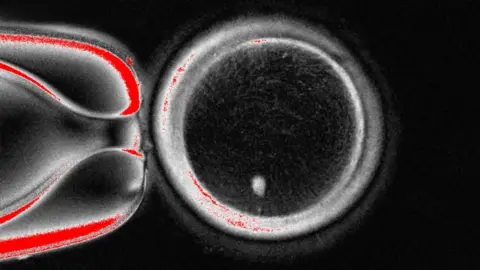

OHSU/Christine Torres HicksUS scientists have, for the first time, made early-stage human embryos by manipulating DNA taken from people’s skin cells and then fertilising it with sperm.

The Oregon Health and Science University research team’s technique takes the nucleus – which houses a copy of the entire genetic code needed to build the body – out of a skin cell.

This is then placed inside a donor egg that has been stripped of its genetic instructions.

OHSUHowever, this egg is not ready to be fertilised by sperm as it already contains a full suite of chromosomes.

You inherit 23 of these bundles of DNA from each of your parents for a total of 46, which the egg already has.

So the next stage is to persuade the egg to discard half of its chromosomes in a process the researchers have termed “mitomeiosis” (the word is a fusion of mitosis and meiosis, the two ways cells divide).

The study, published in the journal Nature Communications, showed 82 functional eggs were made. These were fertilised with sperm and some progressed onto the early stages of embryos development. None were developed beyond the six-day-stage.